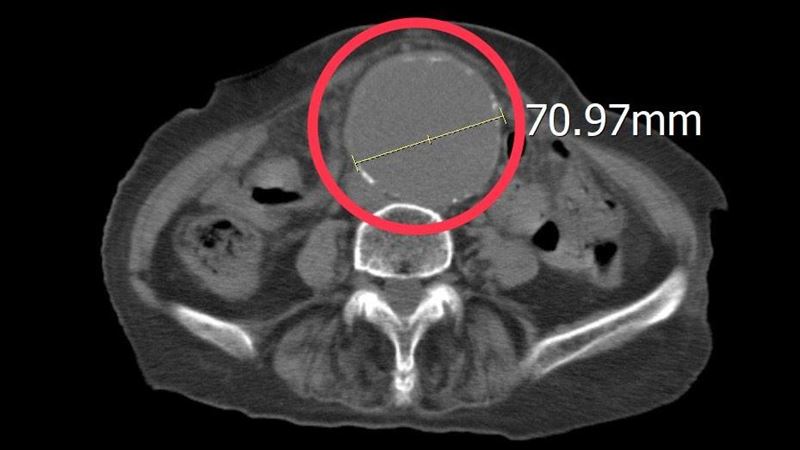

86歲阿嬤由家屬陪同到急診求診時,一再強調她左側下肢痠痛及腰部不適,沒有明顯外傷,但疼痛指數已達到8至10分。為了快速釐清病情,孫秀正醫師立即為病人進行床邊超音波檢查。透過即時影像檢查,發現患者的腹主動脈明顯擴張,直徑已超過7公分,高度懷疑為腹主動脈瘤,進一步安排電腦斷層檢查確認診斷,結果顯示確實為大型腹主動脈瘤。

孫秀正醫師表示,腹主動脈瘤,是腹部主動脈血管壁因退化或動脈硬化而逐漸擴張,當血管直徑持續增大,血管壁會變得脆弱,一旦發生破裂,可能在短時間內造成大量內出血,死亡率極高。當腹主動脈瘤直徑大於5至5.5公分時,破裂風險即明顯增加,而該患者的腹主動脈瘤已超過7公分,屬於極高風險狀態,因此必須爭取時間儘速處理。